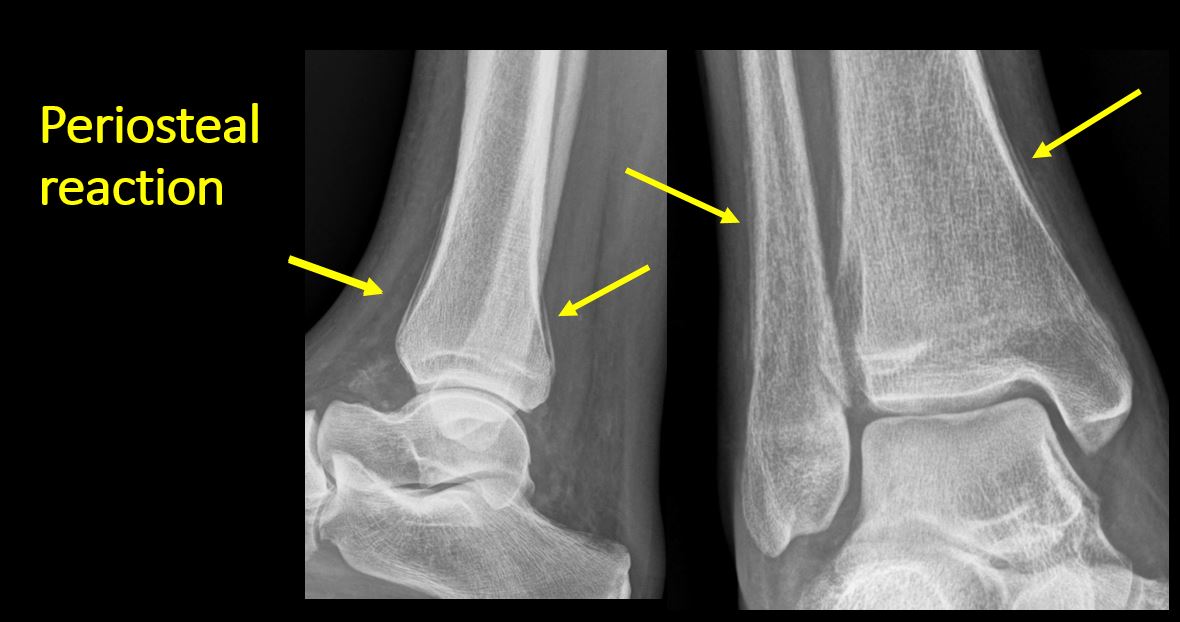

There is periosteal or endosteal reaction which could indicate a healing or subacute fracture or other abnormality. |

No | NA |